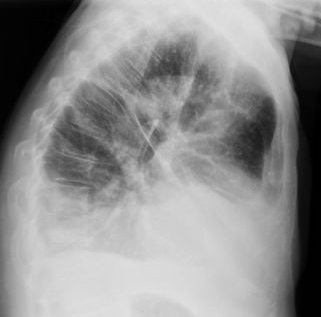

Neumonía basal derecha